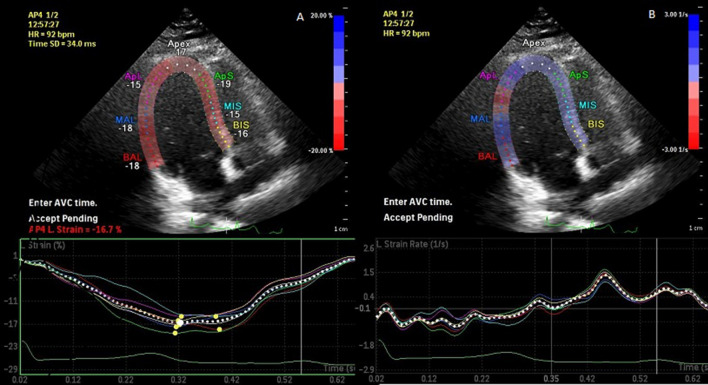

The initial phase in strain analysis is determining the aortic valve closure (AVC) time by employing conventional or AFI methods. Aortic valve closure was identified at baseline and at each grade of procedure in the apical 3-chamber view. We determined the AVC time automatically with the help of the software at the end of the T wave. The accuracy of the timing was validated by identifying the AVC visually using the B-mode image, and before finalizing its electrocardiographic location, the necessary adjustments were done. We started measurement from the basal septum, manually placing 6 or 7 equally distributed endocardial points. Using these points, the 2D speckle tracking algorithm followed the endocardium as the region of interest (ROI) to determine the wall thickness along the heart cycle. ROI consisted of three concentric lines representing the endocardial and epicardial margins and the middle myocardial layer. The required settings were made to match the myocardial thickness, excluding the pericardium. The left ventricle, 4-chamber, 3-chamber, 2-chamber images were analyzed using STE. Furthermore, strain parameters of each segment were evaluated by employing the AFI protocol (Fig. 1).

Fig. 1.

Longitudinal strain (A) and strain rate (B) measurement with two-dimensional speckle tracking echocardiography in an apical four-chamber view